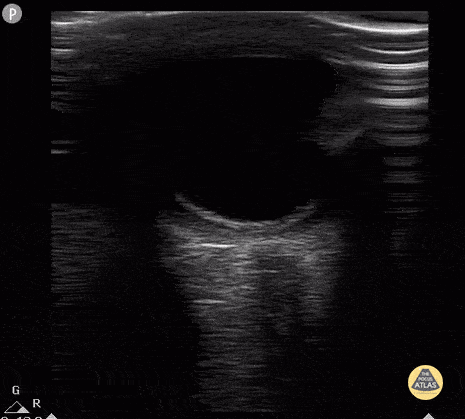

12 year old with subtle retinal detachment (vision 20/400 in affected eye). Dilated eye exam with Inferior retinal detachment from 3 o'clock to 9 o'clock. Contributor: Antonio Riera, MD